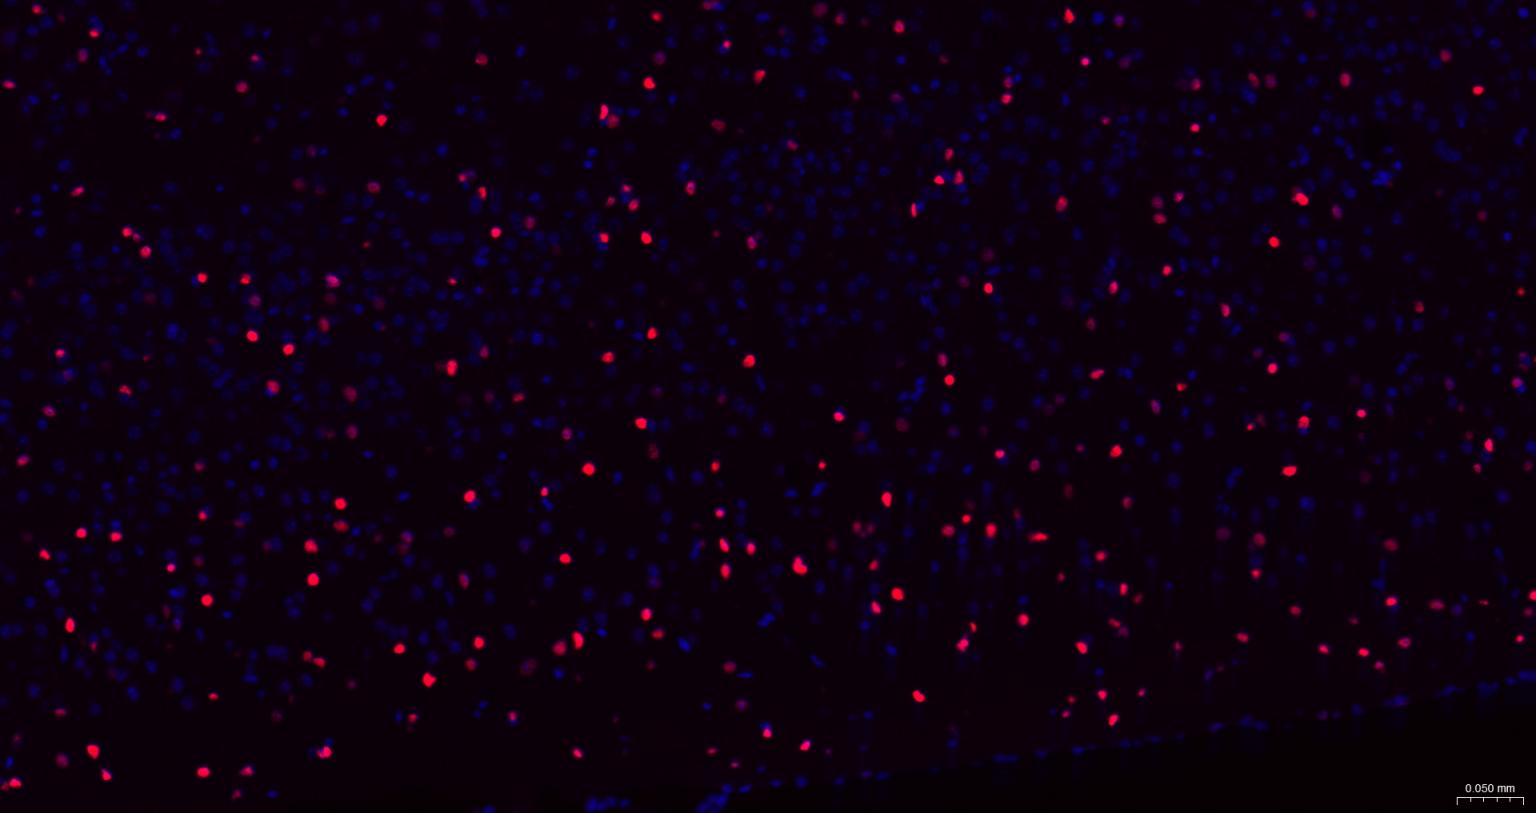

Paraformaldehyde-fixed, paraffin embedded Mouse Cerebrum; Antigen retrieval by boiling in sodium citrate buffer (pH6.0) for 15 min; The section was incubated with SOX2 Monoclonal Antibody, Unconjugated (bsm-60788R) at 1:200 overnight at 4°C. Followed by conjugated Goat Anti-Rabbit IgG antibody (Red, bs-0295G-BF594), DAPI (blue, C02-04002) was used to stain the cell nuclei.